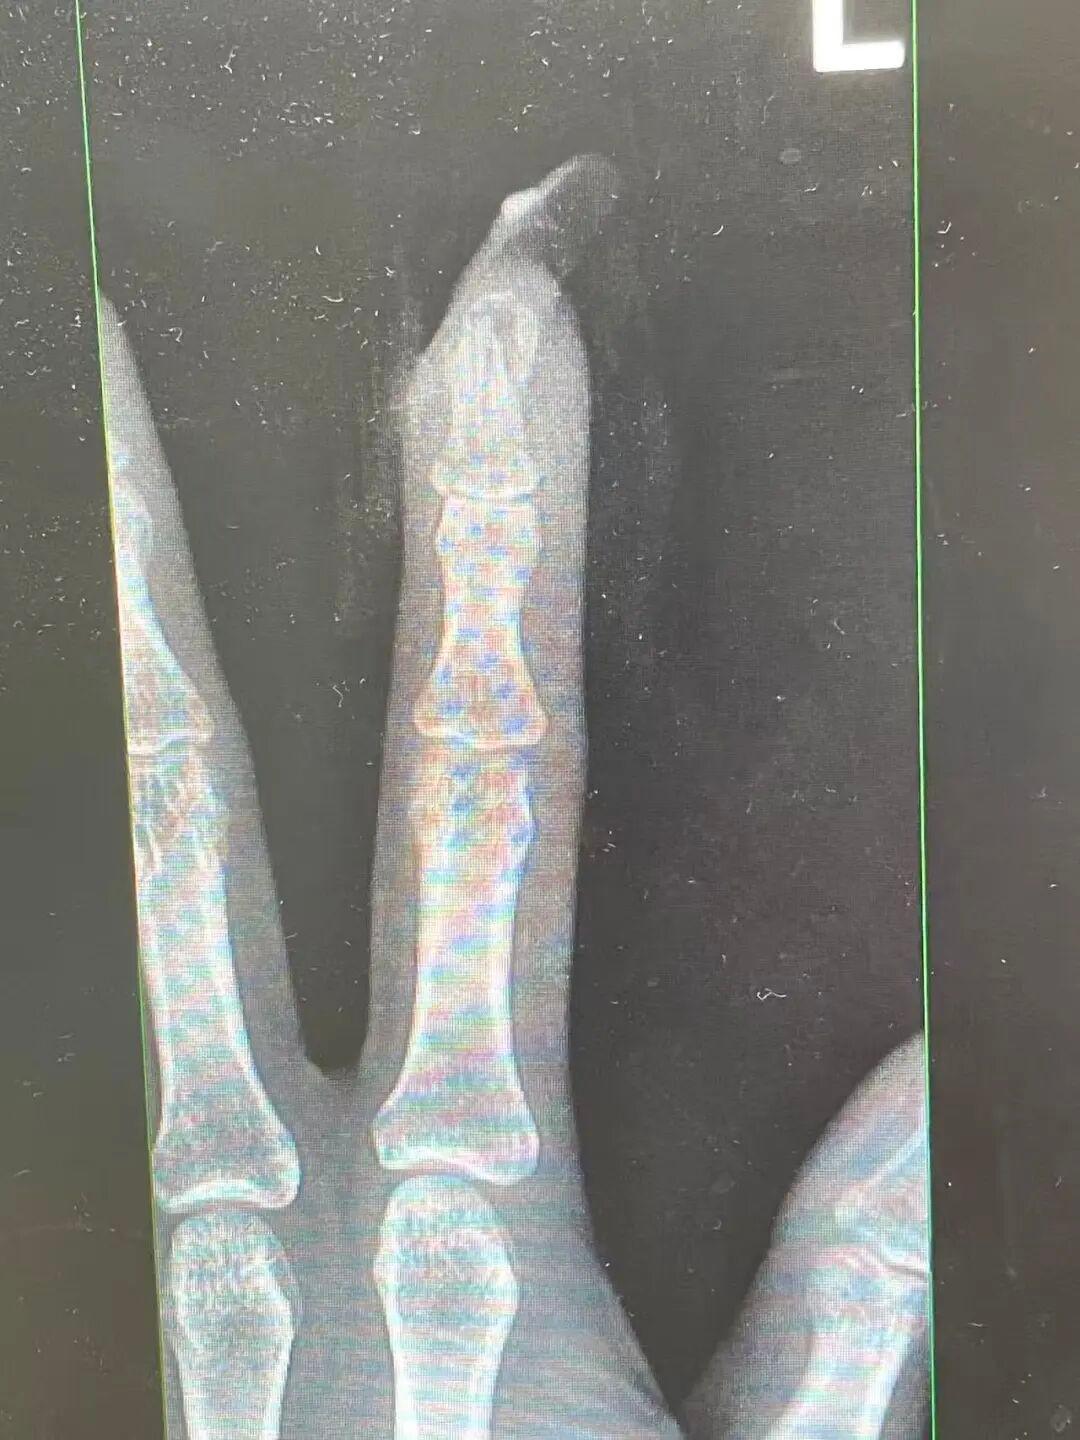

“食指指骨骨折,甲床翻脸。”接诊的骨科医师曹立查验后发现王女士指甲断裂,部分甲床外露,需要手术竖立。曹医师坐窝为王女士进行指骨骨折闭合复位内固定术,术后规复浩繁。曹医师暗示,若是莫得好意思甲,伤害不会这样严重。